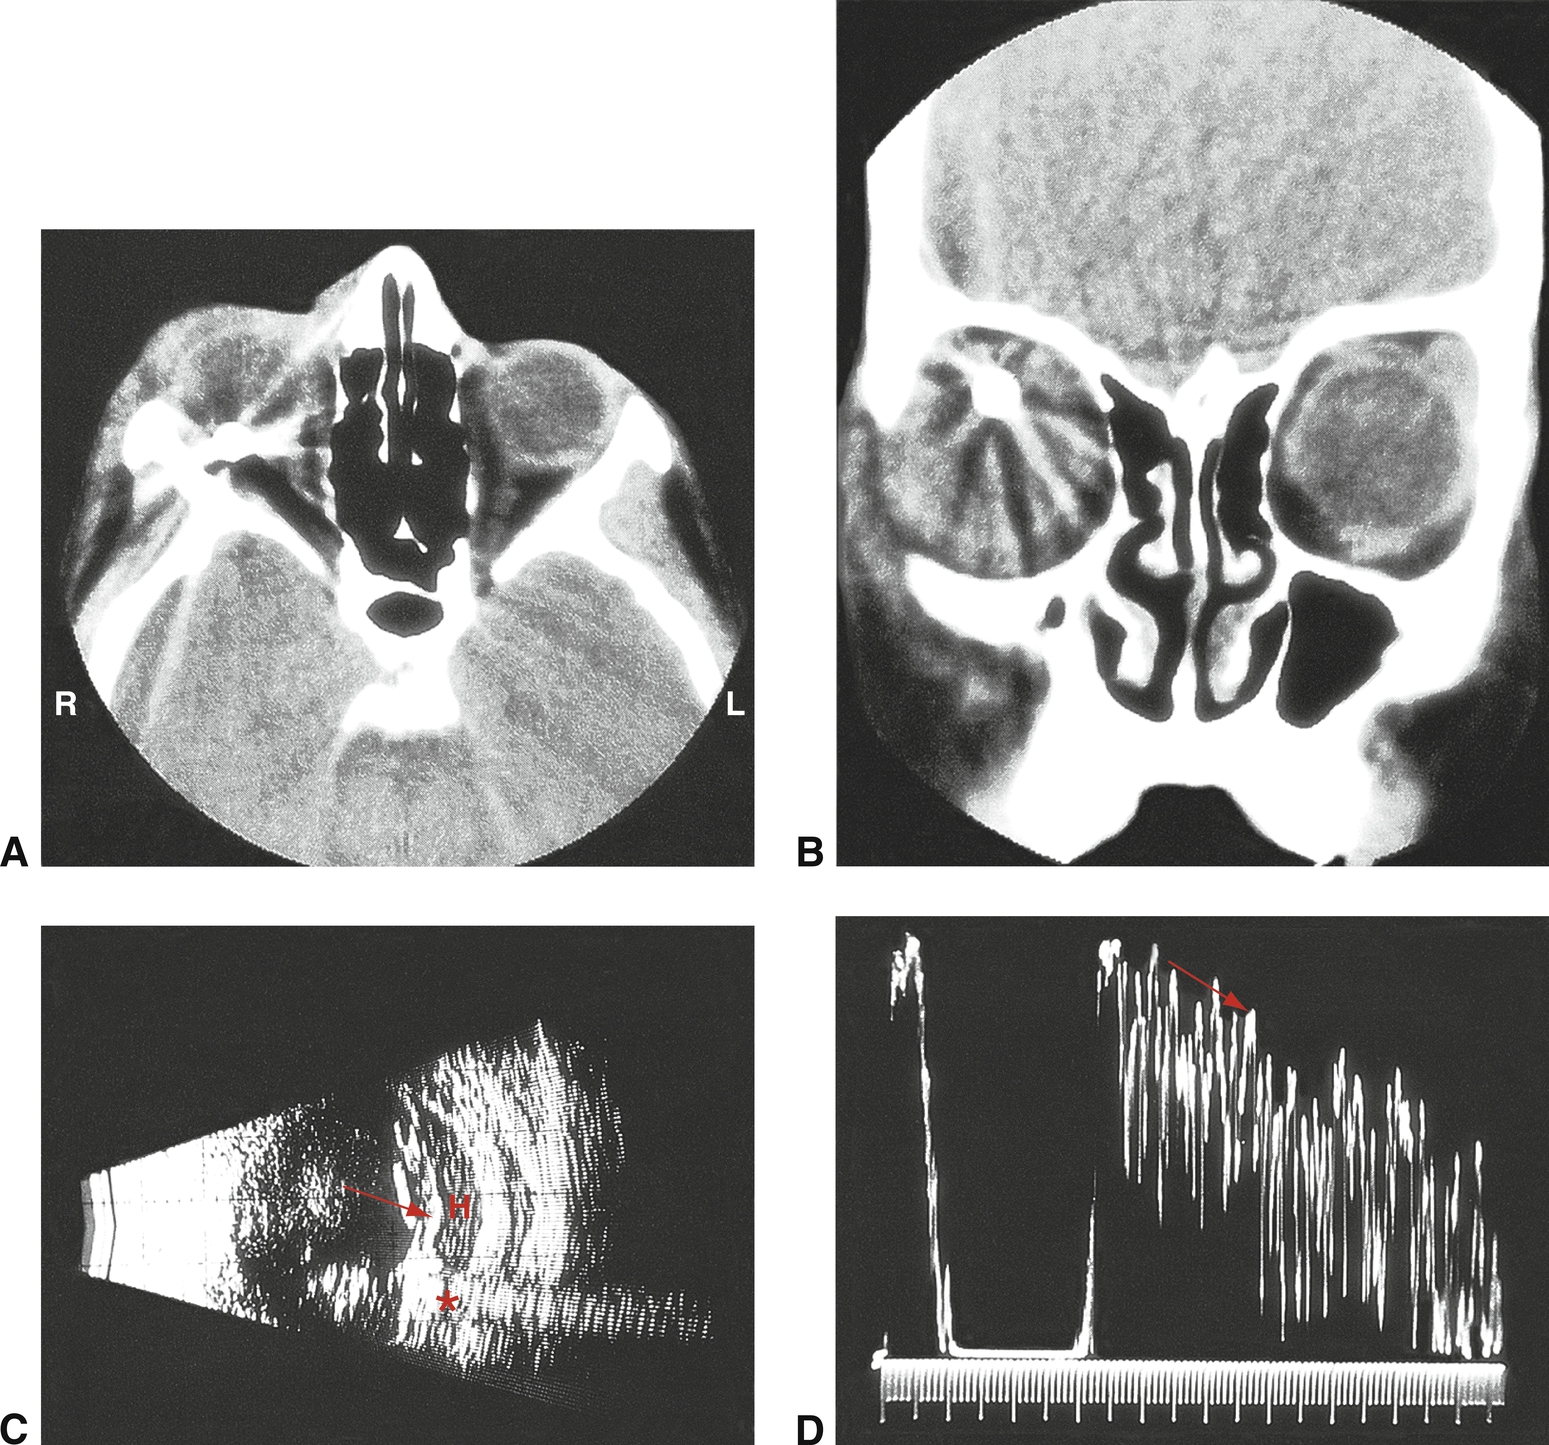

La composition des CEIO a des conséquences en matière d'imagerie médicale. Si un échantillon du matériau dont est composé le CEIO supposé est disponible, on peut l'utiliser afin de déterminer si le CEIO est magnétique, radio-opaque, ou les deux. Si le CEIO est – ou est supposé être – en métal, ou bien si sa composition est inconnue, une IRM est contre-indiquée car la force magnétique pourrait déplacer un CEIO métallique, occasionnant alors des dégâts supplémentaires. En ce qui concerne les matériaux radio-opaques, le scanner se révèle supérieure à toute autre technique lorsqu'il s'agit de visualiser et de localiser le CEIO, tout particulièrement s'il est de taille réduite ou s'il est radio-opaque (fig. 17-6). En l'absence de scanner, une imagerie aux rayons X peut toutefois s'avérer utile si l'on soupçonne la présence de tels CEIO. Les CEIO peuvent également être identifiés et localisés par un praticien expérimenté en technique échographique, ce qui s'avère alors très utile dans le cas de matériaux non opaques.

Un examen échographique peut se révéler nécessaire dans le cas d'yeux présentant une opacité des milieux des suites du traumatisme. Cet examen peut être différé après la suture de la plaie si l'œil blessé est collabé ou afin d'éviter l'expulsion du contenu intraoculaire lorsqu'il s'agit d'une plaie importante et instable. Une quantité importante de gel stérile permet au praticien de recourir à une pression minimale sur la paupière fermée. De l'air intraoculaire peut être à l'origine d'artéfacts qui compliquent l'interprétation de l'échographie. Une tomodensitométrie (TDM) est très utile lorsqu'il s'agit d'examiner les patients chez qui l'on suspecte des corps étrangers intraoculaires. Les corps étrangers métalliques peuvent provoquer des artéfacts qui les font apparaître plus grands que ce qu'ils ne sont en réalité, rendant leur localisation assez difficile. Le bois et le plastique peuvent être difficiles à détecter par TDM, mais peuvent être identifiés et localisés grâce à l'imagerie par résonance magnétique (IRM). Toutefois, l'IRM doit être utilisée seulement après que la présence de corps étrangers ferromagnétiques a été écartée avec certitude, car de tels corps étrangers peuvent être déplacés par le champ magnétique et provoquer alors des dégâts supplémentaires.